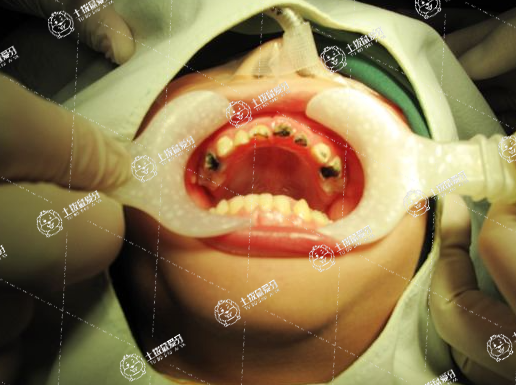

兒童補(bǔ)牙常用的材料主要有以下幾種:

1.樹脂:樹脂是一種丙烯酸樹脂,具有良好的粘附性和耐磨性,是寶寶補(bǔ)牙的首選材料之一。

2.銀汞合金:銀汞合金具有良好的耐磨性和抗腐蝕性,但是含有汞,對(duì)寶寶的健康有一定的風(fēng)險(xiǎn),因此現(xiàn)在已經(jīng)不常用。

3.玻璃離子膜:玻璃離子膜是由玻璃微粒和樹脂組成的一種材料,具有很好的密合性和耐腐蝕性,適用于一些較大的齲洞。

4.不銹鋼:不銹鋼是一種堅(jiān)固耐用、價(jià)格適中的補(bǔ)牙材料,適用于較深的齲洞和較短時(shí)間的暫時(shí)補(bǔ)牙。